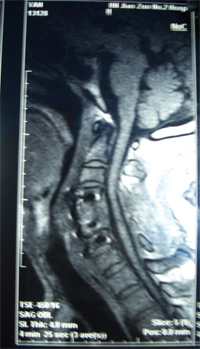

骨科案例

颈椎病手术